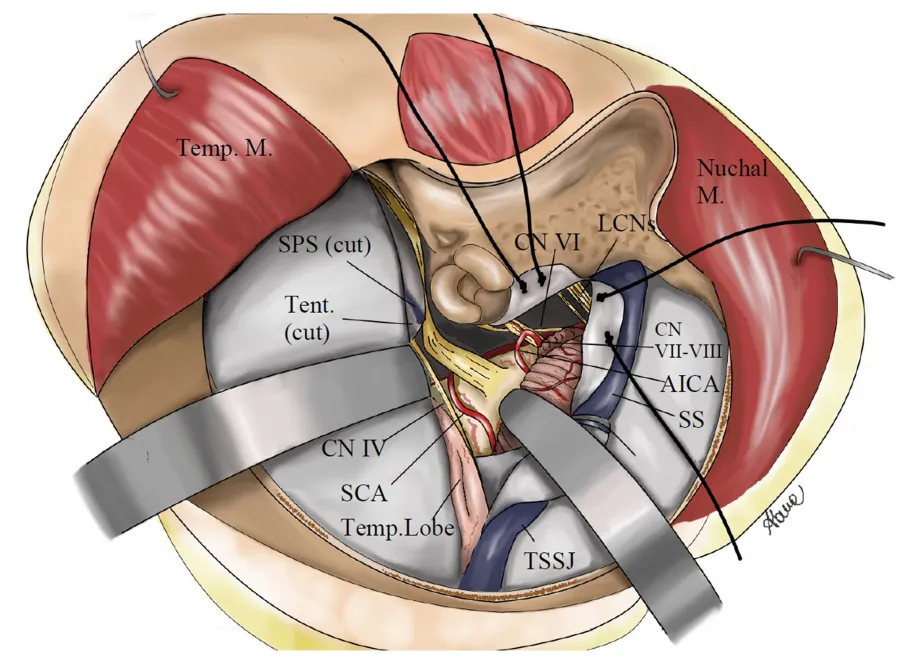

图1为手术通道示意图:展示右侧mini联合经岩骨入路的解剖路径。

Mini-CTPA的核心区域聚焦于岩上窦与横窦交界处,在切开小脑幕和岩上窦后,通过横窦-乙状窦角(TSSJ)移位所创建的颞-小脑间隙来实施操作。图2重点标示了改良皮肤切口(粉色线)与既往CTPA标准切口(绿色线和黑色线)之间的差异及其相应的解剖学优势。

在硬脑膜切开与小脑幕离断阶段,在内淋巴囊周围、后半规管平行处切开乙状窦前硬脑膜,但不切开内淋巴囊,然后在上半规管上方、平行并低于岩上窦处向前延伸。沿岩上窦平行方向切开颞部硬脑膜约1厘米,并在横窦-乙状窦角和横窦上方向后延伸。注意避免损伤Labbe静脉。识别出岩上静脉汇入岩上窦后,在岩上静脉前方结扎并切断岩上窦。然后将小脑幕从后外侧向前内侧切开,直至到达滑车神经入口后方的小脑幕游离缘。随后将横窦-乙状窦角和乙状窦向后下方牵拉,创建出颞-小脑间隙。

选择Mini联合经岩骨入路旨在获得宽阔的幕上幕下联合暴露,并通过多视角安全处理关键的神经血管结构,同时尝试降低入路本身的创伤性。通过Mini联合经岩骨入路的开口,从第III对颅神经到后组颅神经的所有颅神经,以及基底动脉、小脑前下动脉、小脑上动脉和后交通动脉,均可得到安全且充分的暴露。显然,与标准联合经岩骨入路使用的更广泛的肌肉分离和更大的开颅相比,我们未发现暴露范围存在显著差异。此外,在手术结束时,这种改良切口允许以自然的方式轻松重新附着肌肉,并完全覆盖骨窗。